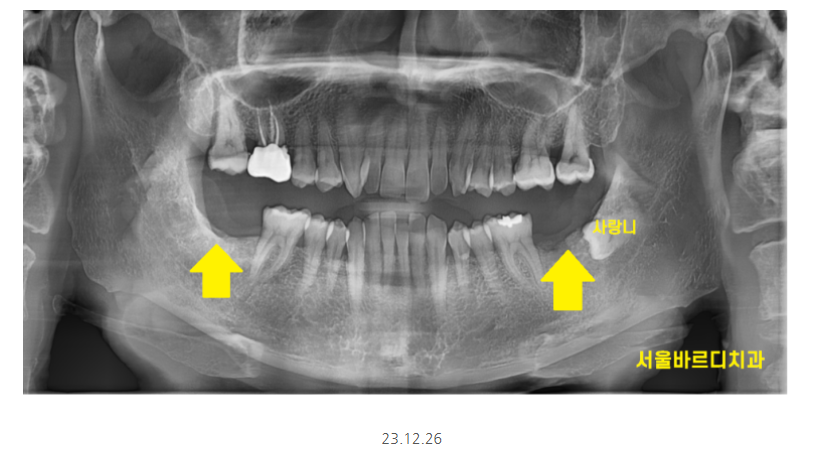

하남시청치과 처음 방문해주셨을 때

왼쪽, 오른쪽 맨 아래 끝에 어금니가 상실한 채로 오셨습니다.

ct를 분석하여

임플란트가 들어갈 각도, 사이즈 분석해줍니다!!

1)ct를 통해 분석